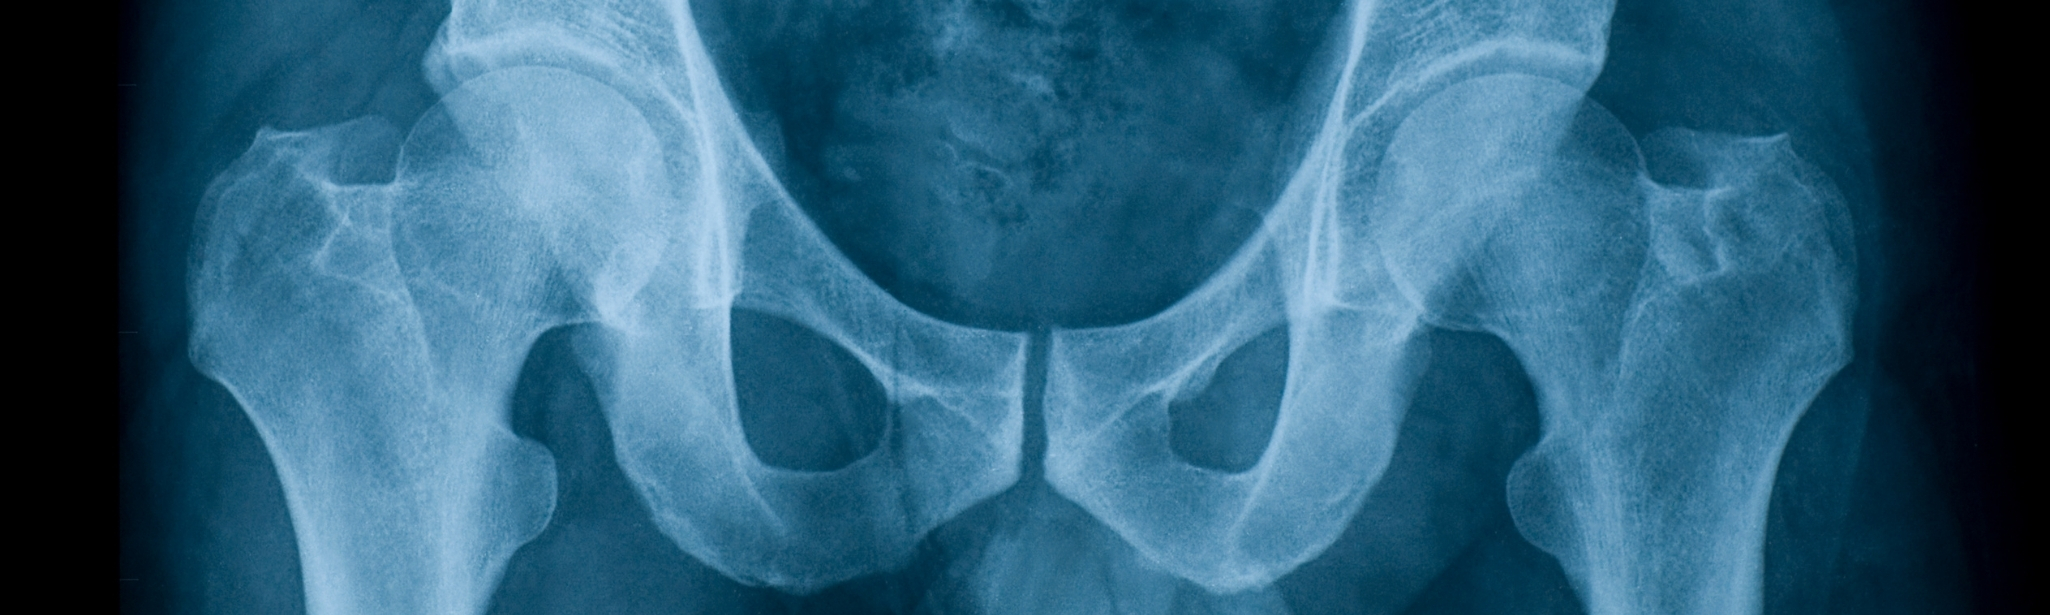

Broken Pelvis Body Cast

Broken Pelvis Body Cast 116 photos